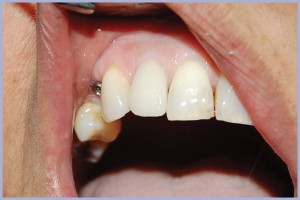

Nel giugno del 2011 si è presentata alla nostra osservazione, presso il reparto di implantologia dell’Università degli Studi di Cagliari, una paziente di 48 anni alla quale mancavano numerosi elementi dentari (Fig. 1). La richiesta della paziente è stata quella di poter essere riabilitata con protesi fissa, ma di dare precedenza all’incisivo laterale superiore destro che le procurava dolore e disagio estetico (Fig. 2).

- Fig. 2 – Situazione clinica iniziale